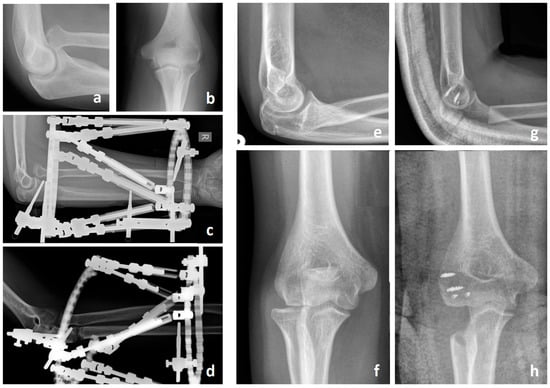

Monteggia fracture-dislocations are a rare injury and comprise only approximately 1–2% of all fractures in children [1]. Monteggia first described the missed Monteggia fracture in 1814. It is characterized by a proximal ulnar shaft fracture with a radial head dislocation and is common between the ages of 4 to 10 years. The usual mechanism of injury is a fall onto a pronated and extended arm [2]. Bado classified Monteggia fractures by defining four subtypes depending on the direction of the radial head dislocation and the angulation direction of the ulna fracture [1]. In children and adolescents, Type I injuries (anterior dislocation of the radial head and anteriorly angulated ulnar shaft fracture) or Type III injuries (lateral or anterolateral dislocation of the radial head and metaphyseal ulnar fracture) are most common [3]. With early identification and appropriate treatment with closed reduction and casting, reduction and intramedullary nailing or plating, Monteggia fracture-dislocations show excellent recovery (Figure 1). Unfortunately, this injury is missed in up to 25–50% of the cases due to only subtle signs and symptoms, and only if a greenstick or plastic deformation of the ulna or re-dislocation due to incorrect immobilization is present [4,5]. If the fracture-dislocation persists for more than 4 weeks, it is defined as chronic Monteggia or a missed Monteggia injury [6]. In most of the neglected radial head dislocations, there are no, or only mild, symptoms. Usually, it is diagnosed several months after the trauma when patients complain of moderate pain in the elbow and restricted movement [7]. Due to complex post-traumatic changes, the initial moderate flexion deficit increases due to the excessive growth of the radius compared to the already shortened ulna. A progressive valgus deformity occurs due to the abnormal growth of the radial column with posterolateral instability [8,9]. In addition, the radial head loses its concavity and forms a so-called “mushroom deformity” [10,11]. Similarly, the surfaces of the proximal radioulnar joint (PRUJ) develop abnormally due to the lack of articulation and become incongruent with a loss of concavity on the articular surface and hypertrophy of the humeral capitulum and lateral epicondyle [5,12]. Ultimately, this process ends in painful radiocapitellar osteoarthritis and neuropathy of the ulnar nerve [13]. Hardly any other injury is more dependent on chronicity and the associated anatomical changes. While fracture-dislocations can typically be treated with minimal effort that results in excellent outcomes, Monteggia injuries that have been missed for many years require complex treatment methods. In this review, we aimed to analyze and summarize the treatment options described in the literature for missed Monteggia injuries. We then propose developing a specific treatment algorithm based on the chronicity of the injury and the presence of dysplastic changes.

Figure 1. Appropriate identification and treatment of acute Monteggia fracture-dislocations for Bado Typ I (a,c) and Typ III (e) in children with closed reduction and casting (b), intramedullary nailing (d) or plating (f).